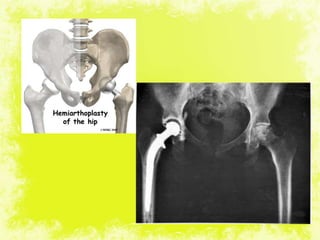

Fracture neck of femur

Undisplaced Displaced

Physiologically <60 years Physiologically >60 years

Closed reduction under x-ray control Prosthetic replacement

Reduction possible Reduction not possible Normal hip Hip with pre existing

arthritis

Multiple screw

fixation

Open reduction

screw fixation

hemiarthroplasty THR

Conservative

Multiple screws

THRHemireplacement arthroplasty

Bipolar arthroplasty